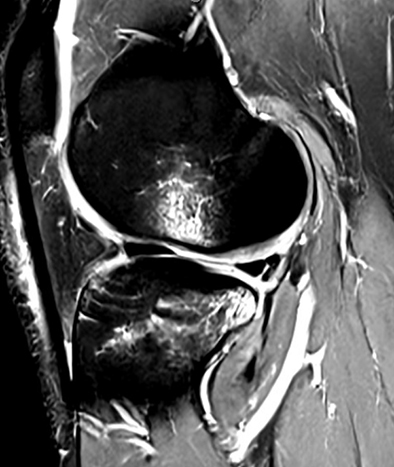

Figure 1

Subchondral bone fractures can happen when the load on the joint is transmitted beyond the protective measures of the menisci, which are shock absorbers, and the articular cartilage. Seemingly minor injuries which results in meniscal injuries increase femoral tibial axial contact pressures. These alter the normal knee biomechanics, which can cause a subchondral knee fracture (Figure 1). In addition subchondral fractures, sometimes referred to as bone bruises, can also occur from direct impact to the knee during activity.